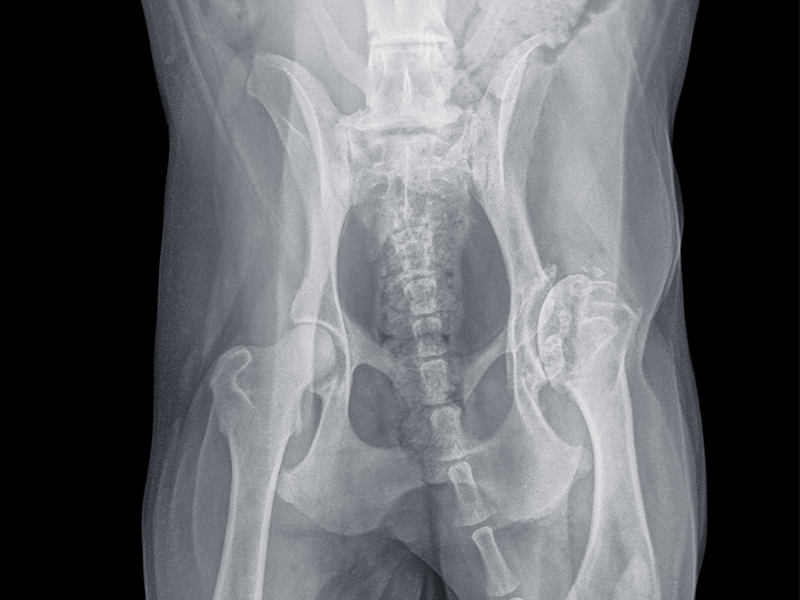

X-ray 기반 고관절 구조 분석

성장 단계와 관절 손상 정도에 따라 수술 선택지가 달라집니다.

골반절골술

골반 각도를 조정해 구조를 교정하는 수술입니다.

• 젊은 연령에서 시행

• 사전 평가 필수